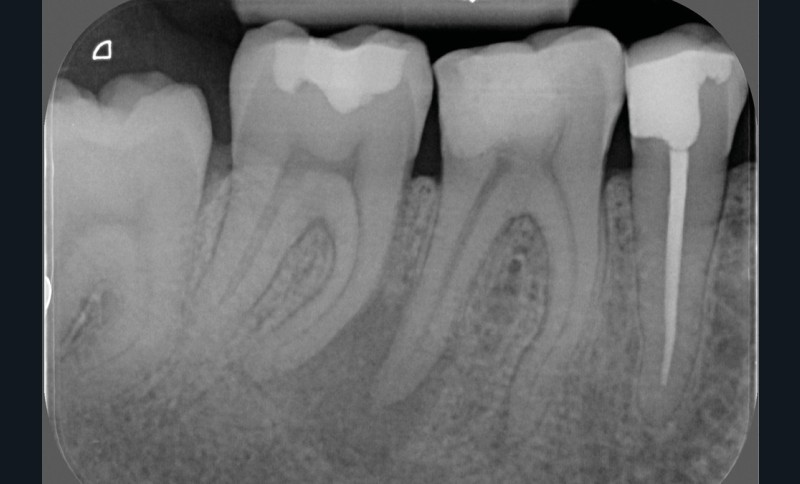

La préparation mécanique est principalement réalisée à l’aide d’instruments NiTi utilisés en rotation continue ou en réciprocité selon une approche corono-apicale. La mise en forme est ainsi plus rapide et respecte mieux le trajet canalaire initial qu’avec une instrumentation manuelle. Le diamètre apical et la conicité de la préparation canalaire font toujours débat. Ils dépendent de l’anatomie initiale et doivent permettre une irrigation efficace sans fragiliser la dent. Ainsi, un diamètre apical de 30 et une conicité de 6 % sont souvent proposés comme objectif minimal à atteindre [3] (fig. 1).